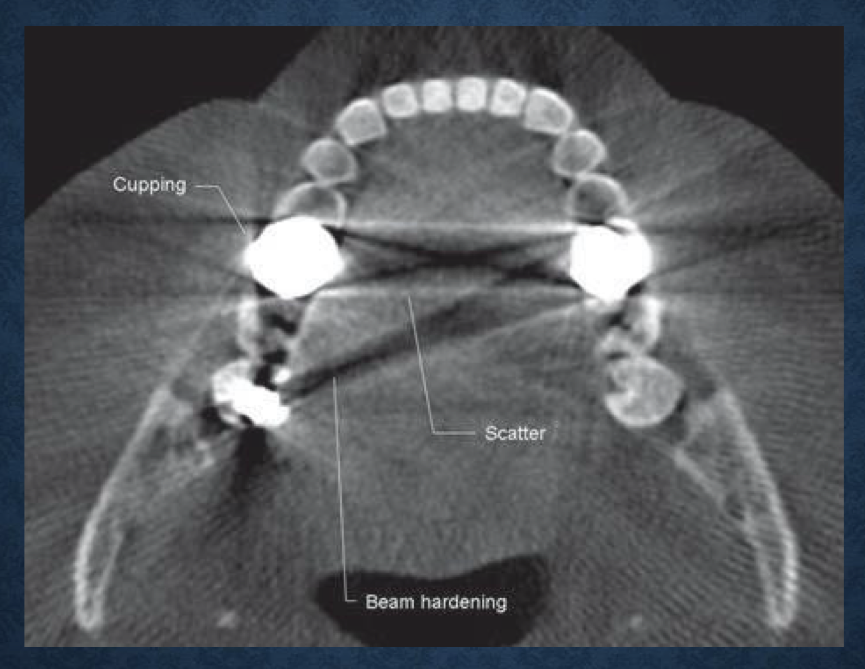

what is this?

axial view demonstrating beam hardening, scatter, and cupping artifacts

aka acquisition artifacts

beam hardening

as an x ray beam passes through an object, lower energy photons are absorbed in preference to higher energy photons

results in 2 types of artifacts- distortion of metallic structures as a result of differential absorption (cupping effect), and streaks/dark bands that can appear between 2 dense objects